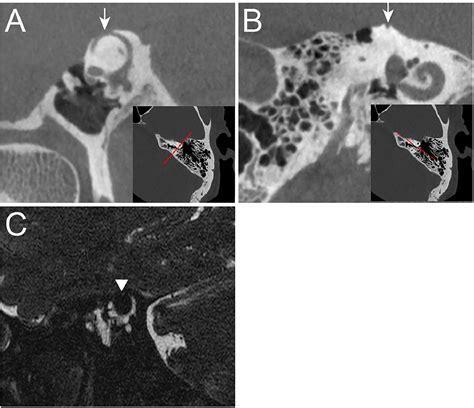

To grasp the complexities of Superior Semicircular Canal Dehiscence, one must first understand the role of the semicircular canals. These structures are vital for balance, filled with fluid that helps the brain track rotational movement. Typically, these canals are encased in solid bone. In patients with SSCD, a small opening or "dehiscence" forms in the superior canal, usually due to developmental defects or prolonged physical stress. This opening acts as a third window, allowing sound and pressure waves to interact directly with the vestibular system, which is not how the ear is designed to function.

Because the inner ear is now hyper-sensitive to pressure changes, even minor stimuli can trigger debilitating symptoms. This phenomenon is known as the third window effect, where sound energy that would normally be funneled to the cochlea for hearing is instead shunted through this abnormal opening, leading to dizziness, vertigo, and unusual auditory sensations.

High-Resolution CT Scan Visualizing the bony opening in the temporal bone.

💡 Note: A standard CT scan is often insufficient; surgeons require high-resolution, thin-cut scans specifically focused on the temporal bone to detect the minute gap in the semicircular canal.

If symptoms are severe or progress to the point where they interfere with daily activities, surgical intervention is considered. The most common surgical approach is canal plugging or resurfacing. During this procedure, the surgeon accesses the area—usually through the middle cranial fossa or a transmastoid approach—to seal the opening. By plugging the dehiscence, the "third window" is closed, effectively eliminating the abnormal pressure dissipation that causes symptoms.